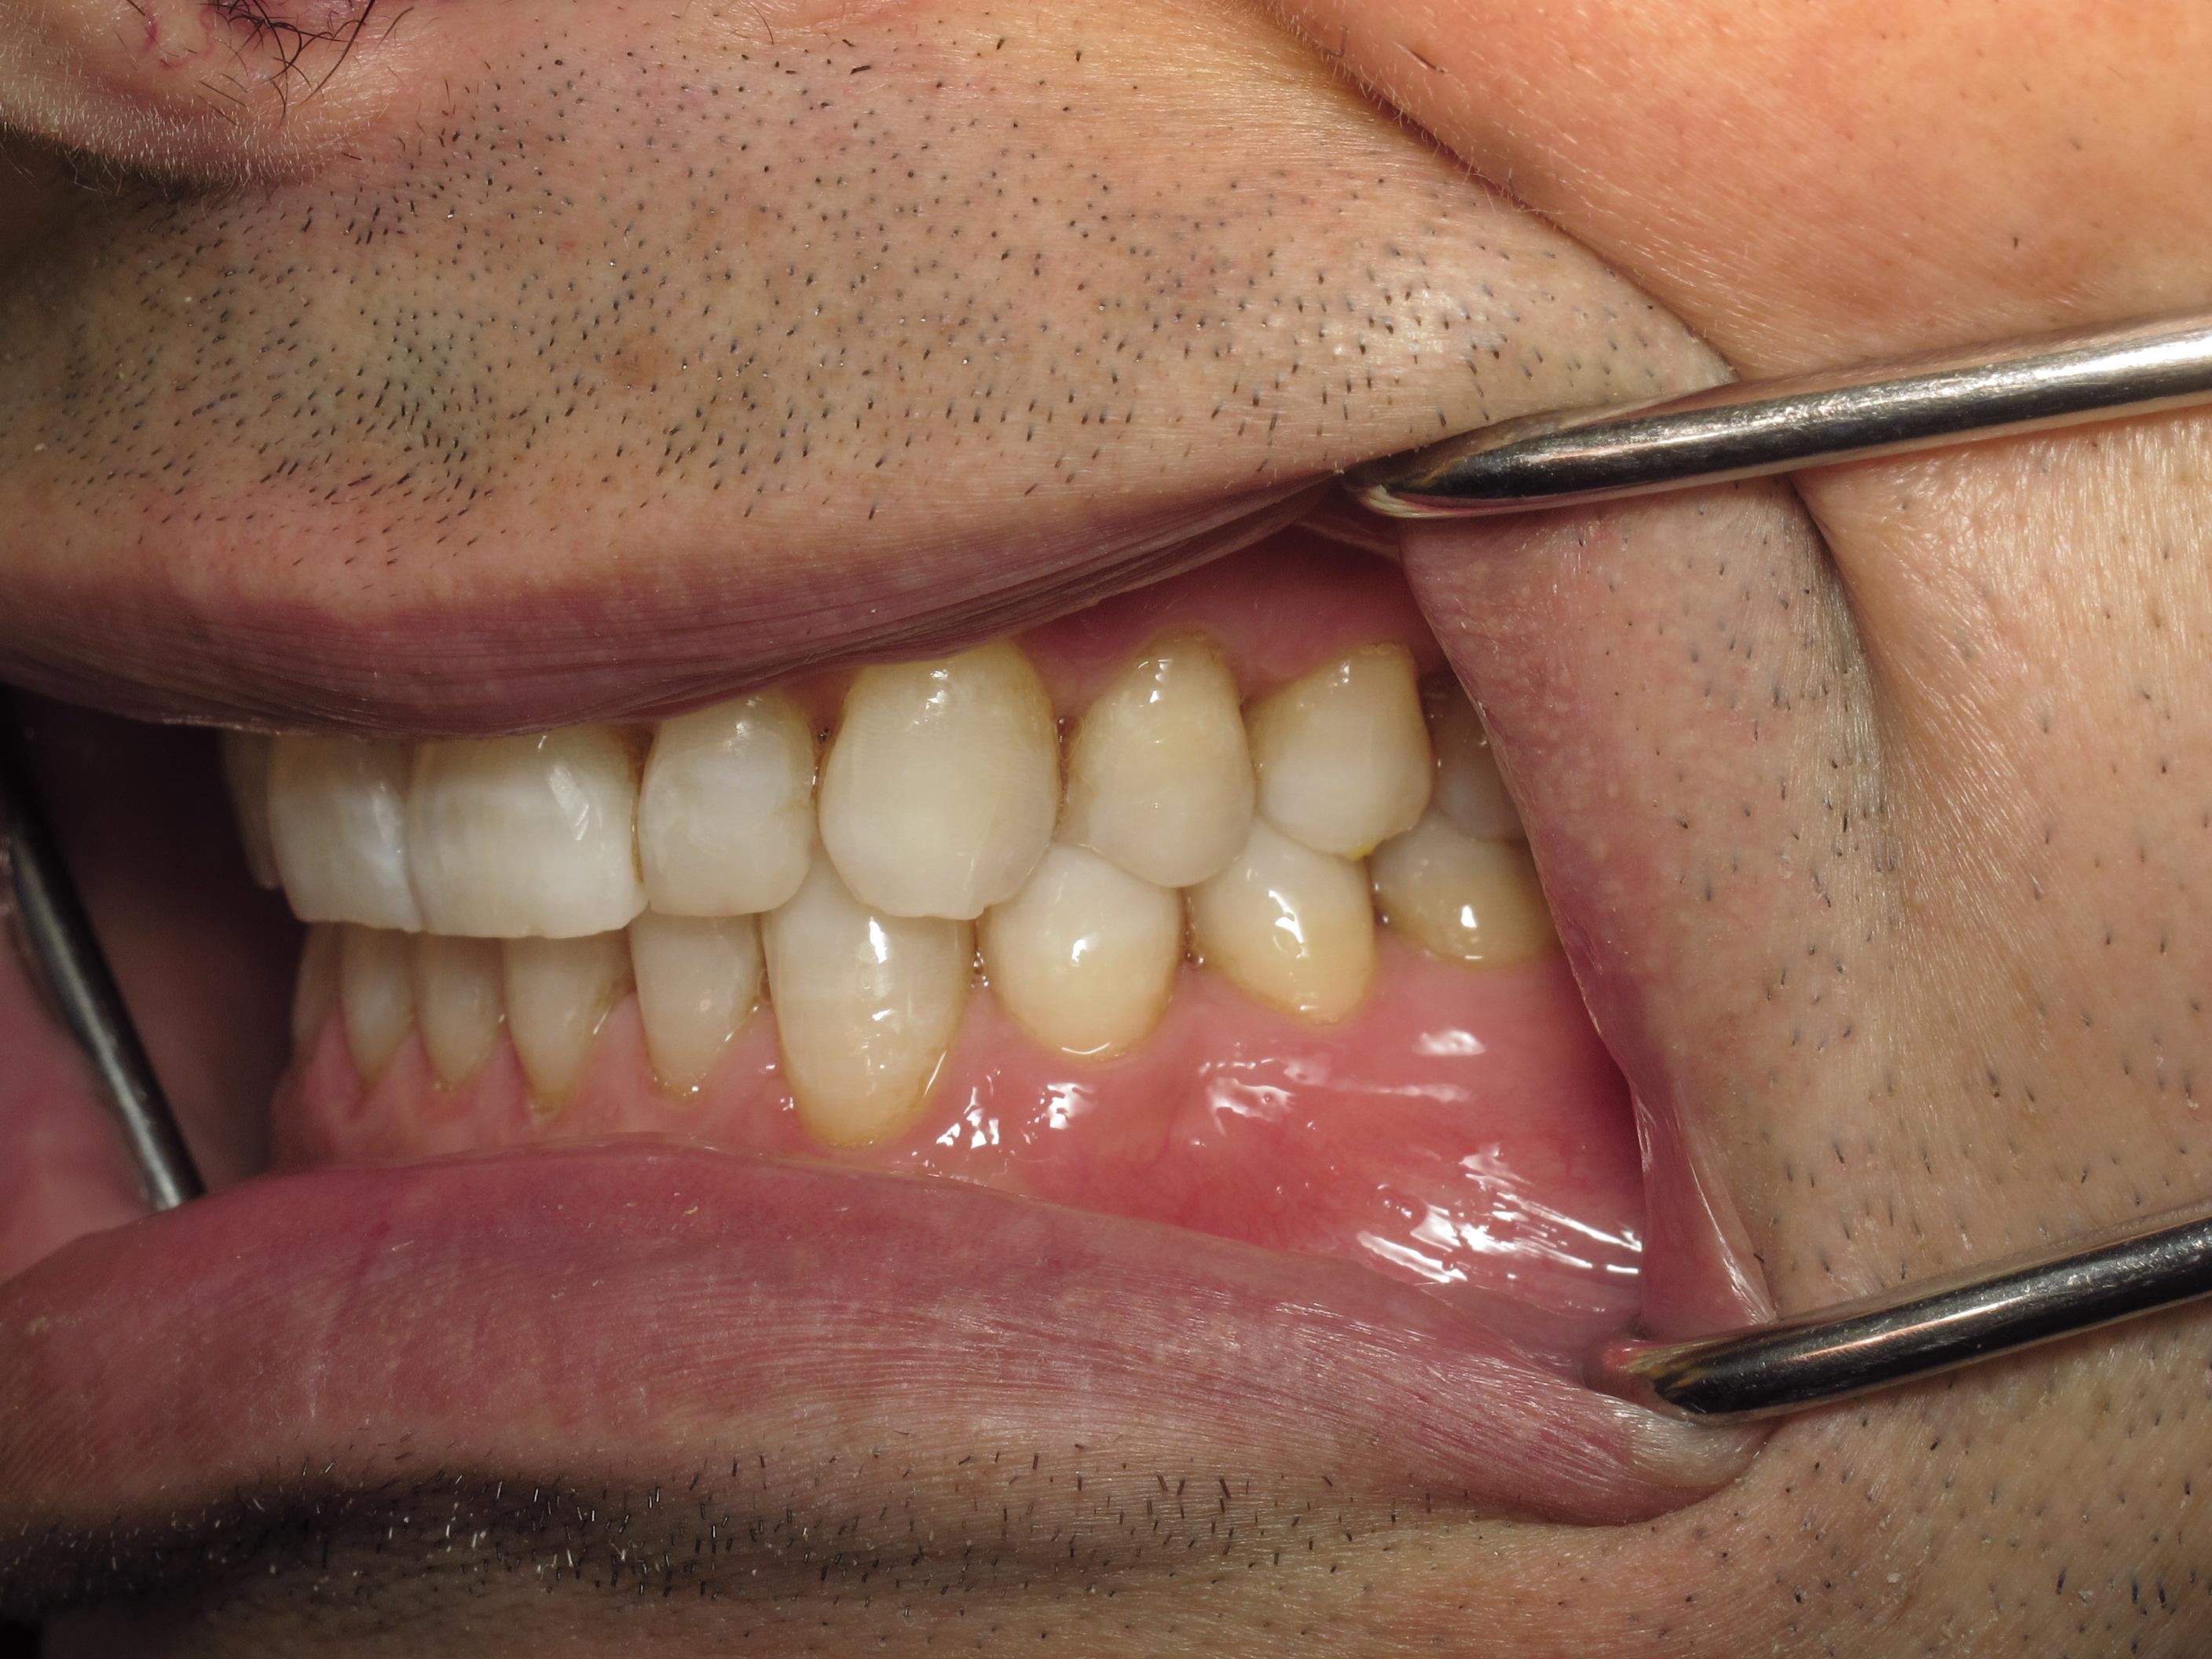

https://demo.discussdentistry.com/forums/topic/accident-victim-upper-arch-rehab/#post-26049 <![CDATA[Accident victim => Upper arch rehab]]> https://demo.discussdentistry.com/forums/topic/accident-victim-upper-arch-rehab/#post-26049 Tue, 30 Apr 2024 04:28:51 +0000 Amit Kumar The patient presents after falling in the bathroom and hitting his face on the countertop.  Previously, he had a PFM crown in the upper anterior.  He needed root canal therapy.

The patient is a stage performer (actor) and has appeared in some minor film roles, so he wanted to restore his teeth so that his smile would appear “white” on camera.

The patient’s lower teeth need attention and we will start the process once the patient’s finances have improved.

eMax material was used.  Pics were taken immediately after cementation.Before LeftBefore FrontBefore RightAfter FrontAfter LeftAfter Right